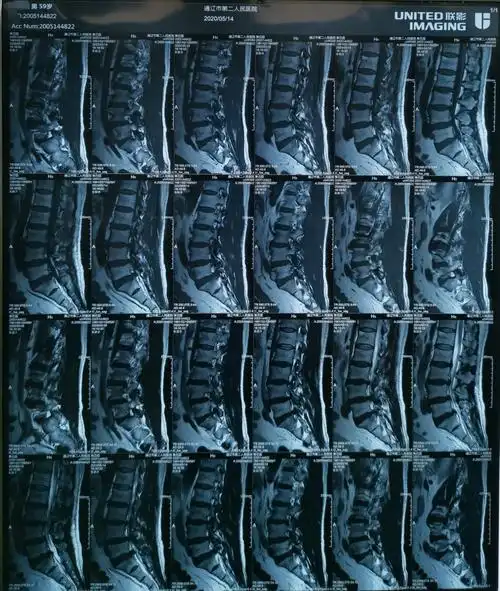

腰间盘突出椎间孔镜手术四例